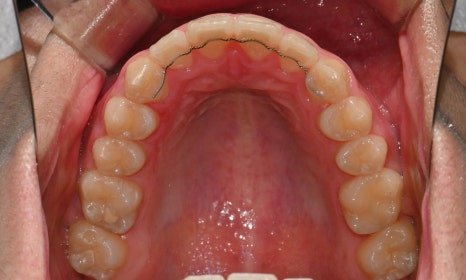

외관상으로는 아랫입술이 돌출되어 보이고 아래 치아가 좌측으로 치우치면서 치아 중심선(midline)이 맞지 않는 상태였습니다. 또한 환자는 어릴 적 넘어지면서 앞니가 깨졌던 외상 병력이 있었고, 그 영향으로 앞니 뿌리가 부분적으로 흡수된 상태였습니다.

2024.12. 초진 구내사진 - 연세정원치과

정밀 검진 결과, 하악 치열이 좌측으로 틀어져 있었고 그로 인해 위아래 치아 중심선이 일치하지 않았습니다. 아래 치열이 전체적으로 전방 위치하여 아래 입술 돌출이 더 도드라져 보이는 상태였습니다. 그리고 상악궁이 하악궁보다 좁아서 앞니 부위 일부 반대로 물리는 치아 교합도 관찰되었습니다. 특히 외상 치아의 경우, 교정력 적용시 추가적인 염증성 치근 흡수 위험이 존재하기 때문에, 치료 중 지속적인 관찰이 필수적인 상황이었습니다.

치료 시작 7개월 후 사진으로, 치아 배열 후 아래 우측에 미니스크류를 식립하여 치아 중심선을 개선하는 중으로, 교합과 치아 중심선이 많이 개선된 것을 확인할 수 있습니다.

약 1년 간의 교정 치료를 통해 어긋나 있던 치아 중심선이 자연스럽게 맞춰졌고, 중심선 비대칭이 개선 및 하악 아랫입술 돌출도 눈에 띄게 호전되었습니다. 무엇보다 치료 기간 동안 앞니의 치근 흡수는 추가적인 진행 없이 안정적으로 유지되었습니다.

돌출을 조금 더 개선하는 것을 추천했으나, 환자가 갑자기 군 입대를 하게 되어 현 상태로 치료를 마무리하기로 하였습니다. 치료 전후 치아 위아래 중심선이 일치하며 좌우 어금니 교합도 향상되었습니다. 하악 치열의 후방 이동으로 아래 입술의 돌출도도 많이 개선되었습니다. 멀리서도 믿고 내원해주고, 치료 기간 동안 성실히 협조해준 환자분께 감사드리며 앞으로도 건강한 치아로 군 생활 잘 마치길 응원합니다 :)